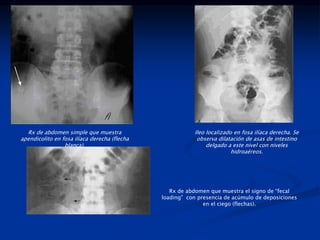

Rx de abdomen simple que muestra

apendicolito en fosa ilíaca derecha (flecha

blanca).

Ileo localizado en fosa ilíaca derecha. Se

observa dilatación de asas de intestino

delgado a este nivel con niveles

hidroaéreos.

Rx de abdomen que muestra el signo de “fecal

loading” con presencia de acúmulo de deposiciones

en el ciego (flechas).